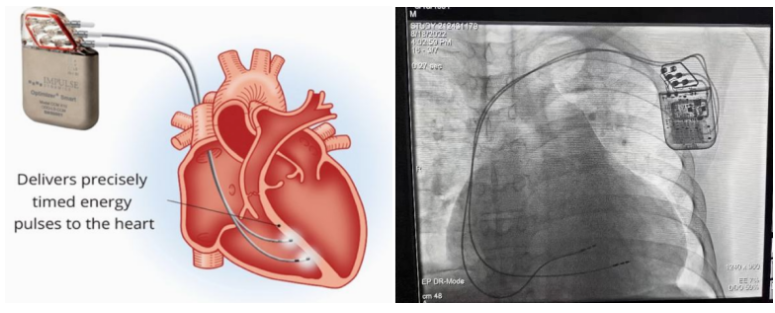

②心臟再同步治療

Cardiac Resynchronization Therapy,CRT

心臟再同步化治療,指雙心室起搏器,是通過雙心室同步起搏的方式,幫助心衰患者實現(xiàn)正常起搏的裝置。CRT包括一個口袋大小的脈沖發(fā)生器和三根電極導(dǎo)線,可被植入人體。通過監(jiān)測心律,在發(fā)現(xiàn)異常后,信號發(fā)生器發(fā)送電流脈沖,刺激心室重新同步,從而改善癥狀,提高患者的心臟泵血效率。目前有兩種類型的CRT裝置:植入式心臟再同步治療起搏器(CRT-P)和植入式心臟再同步治療除顫器(CRT-D)。主要區(qū)別在于后者除了改善心臟收縮同步性外,還具備除顫功能,能及時處理危及生命的室性心律失常,避免猝死。

國內(nèi)研發(fā)企業(yè):無雙醫(yī)療、樂普醫(yī)療、先健科技、創(chuàng)領(lǐng)心律、秦明醫(yī)學(xué)等